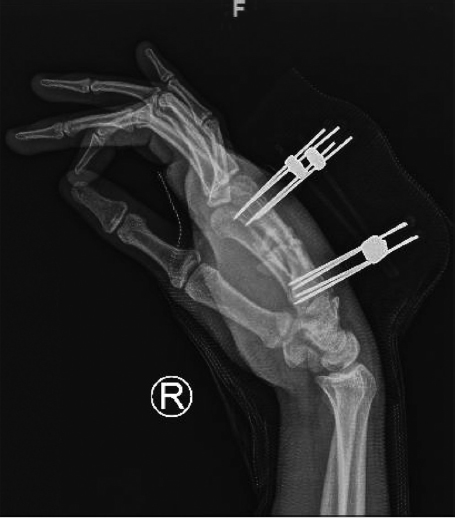

Noncomminuted, displaced fractures that constitute more than 25% ofthe articular surface or exhibit more than 1 mm of articular step-off are treated operatively with K-wires and immobilization. Comminuted fractures require fixation with multiple K-wires or cerclage wires. Unstable reductions may require immobilization for 2 to 3 weeks before range-of-motion exercises are initiated. Skeletal traction or external fixation (► Fig. 38.1, ► Fig. 38.2, ► Fig. 38.3) may be needed if there are associated comminuted fractures of the adjacent base of the proximal phalanx. For open comminuted head fractures, especially fractures with bone loss, prosthetic arthroplasty is a reasonable alternative.